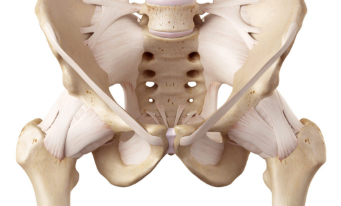

Na Ortopedia Pediátrica, o uso de técnicas modernas e abordagem personalizada são fundamentais para garantir um cuidado de excelência. Cada tratamento é cuidadosamente planejado, considerando as necessidades específicas de cada criança, desde o manejo de fraturas até correções complexas de deformidades congênitas e patologias do quadril infantil.

Displasia do desenvolvimento do quadril (DDQ)

Osteotomia do quadril